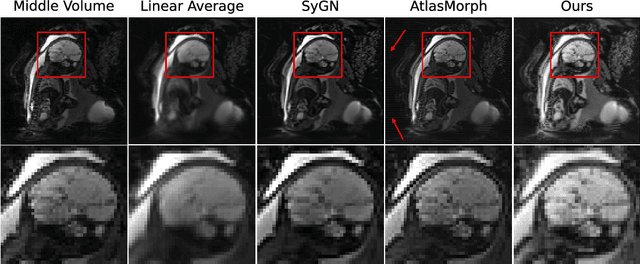

Abstract:We present a method for fast biomedical image atlas construction using neural fields. Atlases are key to biomedical image analysis tasks, yet conventional and deep network estimation methods remain time-intensive. In this preliminary work, we frame subject-specific atlas building as learning a neural field of deformable spatiotemporal observations. We apply our method to learning subject-specific atlases and motion stabilization of dynamic BOLD MRI time-series of fetuses in utero. Our method yields high-quality atlases of fetal BOLD time-series with $\sim$5-7$\times$ faster convergence compared to existing work. While our method slightly underperforms well-tuned baselines in terms of anatomical overlap, it estimates templates significantly faster, thus enabling rapid processing and stabilization of large databases of 4D dynamic MRI acquisitions. Code is available at https://github.com/Kidrauh/neural-atlasing